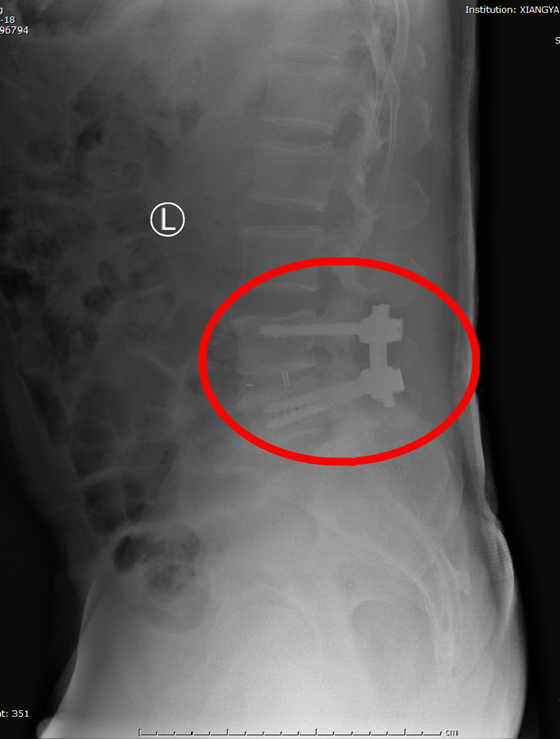

家住湖南澧县的李先生因腰椎间盘突出、腰椎失稳于5月8日入住湘雅常德医院骨科,骨科负责人陈芳田主任医师对患者病情进行详细评估后,建议患者行腰椎内固定融合手术。考虑国家骨科脊柱耗材集采政策即将落地,建议患者住院等待数日,集采通知下发调价后再行手术治疗。

两天后,通知正式下发。我院积极响应,调整脊柱耗材价格,手术准备完善后,于5月12日顺利为李先生完成了首台脊柱集采后腰椎内固定融合手术,原本集采前脊柱内固定融合耗材价格约为25000元,集采后价格降至4300元,极大减轻了患者手术费用负担。李先生直言“感谢国家的好政策!让很多像我这样长期忍受病痛折磨,又受限于经济压力,迟迟无法接受手术治疗的患者看到了希望的曙光。”